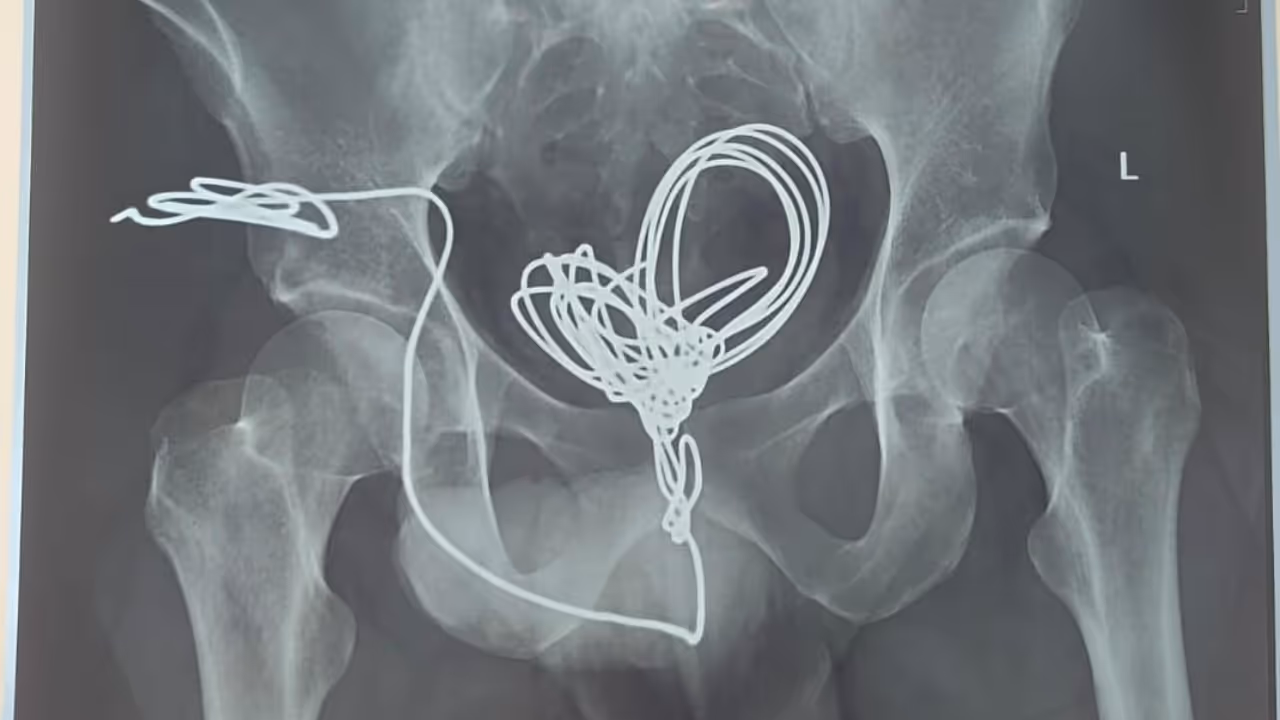

തിരുവനന്തപുരം: മൂത്രനാളിയിലൂടെ സ്വയം കുത്തിക്കയറ്റിയ ഇലക്ട്രിക് വയർ യുവാവിന്റെ വയറ്റിൽ നിന്ന് ശസ്ത്രക്രിയയിലൂടെ പുറത്തെടുത്തു. തിരുവനന്തപുരം സ്വദേശിയായ 25കാരനാണ് മൂന്ന് മീറ്ററോളം നീളമുള്ള ഇലക്ട്രിക് ഇൻസുലേഷൻ വയർ മൂത്രനാളിയിലൂടെ കുത്തിക്കയറ്റിയത്. ആശുപത്രിയിലെത്തുമ്പോൾ വയർ മൂത്രസഞ്ചിയിൽ കുരുങ്ങിക്കിടക്കുന്ന നിലയിലായിരുന്നു. എന്നാൽ യുവാവ് ഇതു ചെയ്തതിന്റെ കാരണം വ്യക്തമല്ലെന്ന് അധികൃതർ പറഞ്ഞു.

തിരുവനന്തപുരം മെഡിക്കൽ കോളജ് ആശുപത്രി യൂറോളജി വിഭാഗത്തിൽ വയർ തുറന്നു നടത്തിയ ശസ്ത്രക്രിയയിലൂടെയാണ് പല കഷ്ണങ്ങളായി മുറിച്ച് ഇലക്ട്രിക് വയർ പുറത്തെടുത്തത്. ശസ്ത്രക്രിയ രണ്ടര മണിക്കൂറോളം നീണ്ടു. ശസ്ത്രക്രിയയ്ക്ക് ശേഷം തീവ്രപരിചരണ വിഭാഗത്തിൽ ചികിത്സയിൽ കഴിയുന്ന യുവാവ് സുഖം പ്രാപിച്ചു വരുന്നതായി ആശുപത്രി അധികൃതർ അറിയിച്ചു.